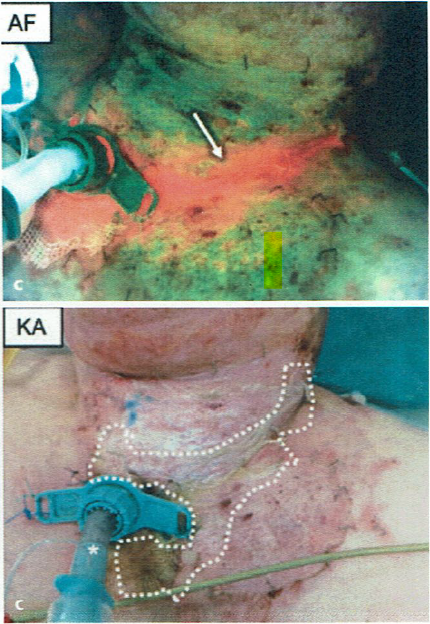

Multidisciplinary Strategies With Real-Time Fluorescence Images and Negative Pressure Wound Therapy to Manage Organ/Space Surgical Site Infection in Transplanted Kidneys

Chen, CH et al. Annals Plastic Surgery 2023

The use of the MolecuLight i:X in managing burns: a pilot study

Blumenthal, E et al. J Burn Care Research 2018

Imaging of bacteria in burn wounds treated with split thickness grafts in MEEK/MESH technique: a pilot study with first experiences in clinical wound evaluation with autofluorescence

Alawi, SA et al. HMPC 2019 (Article in German)